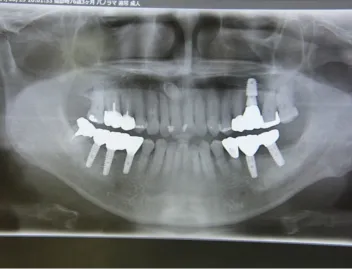

施術を検討されている方に様々なケースの施術前後の違いをご確認いただけるよう、インプラントやインビザラインでの矯正の症例を画像も用いて一覧にして載せております。「ずれている前歯を揃えたい」「受け口を直したい」「抜けた歯をキレイに整えたい」など、様々なご相談を承り、ご予算や仕上がりのご要望はもちろんのこと、長期的な口腔の健康維持も考慮したプランをご提案いたします。